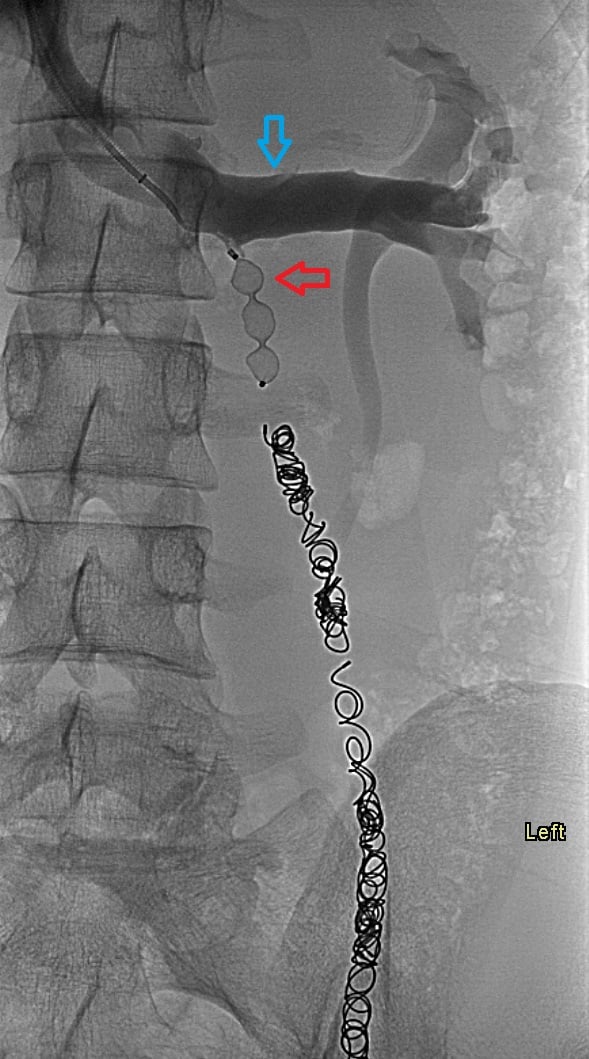

17-year-old male with a long history of left-sided varicoceles status post surgical ligation in 2015 presents with recurrence of symptoms, referred to us for left gonadal vein embolization.

Ultrasound demonstrates enlarged veins (>3 mm) adjacent to the testicle. Angiogram demonstrates reflux of contrast into the left gonadal vein to the level of the scrotum, indicating venous valvular incompetence. Coil embolization and sotradecol sclerotherapy of the left gonadal vein were performed, with an Amplatzer plug at the top of the vein. Repeat angiogram demonstrates no contrast opacification of the vein. Red arrows indicate the left gonadal vein and the blue arrows indicate the left renal vein.

The patient's symptoms have resolved.